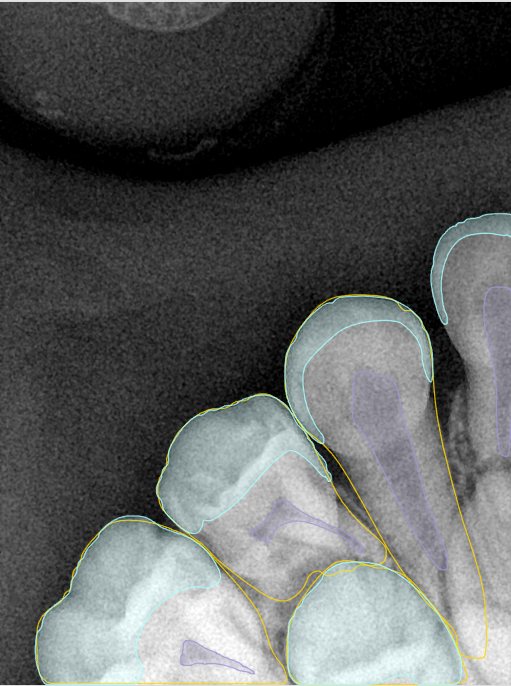

CR/DR 牙齿分割阶段记录

当前进展

- 完成了 CR/DR 牙齿相关分割训练

- 当前结果已经达到阶段预期,但仍有细节问题需要继续处理

相关测试

遇到的问题

- 训练过程中出现过 mask 下移问题

- 部分结果会出现 box 填充异常

- mask 边缘仍然有比较明显的锯齿感

参考

第二版算法问题测试